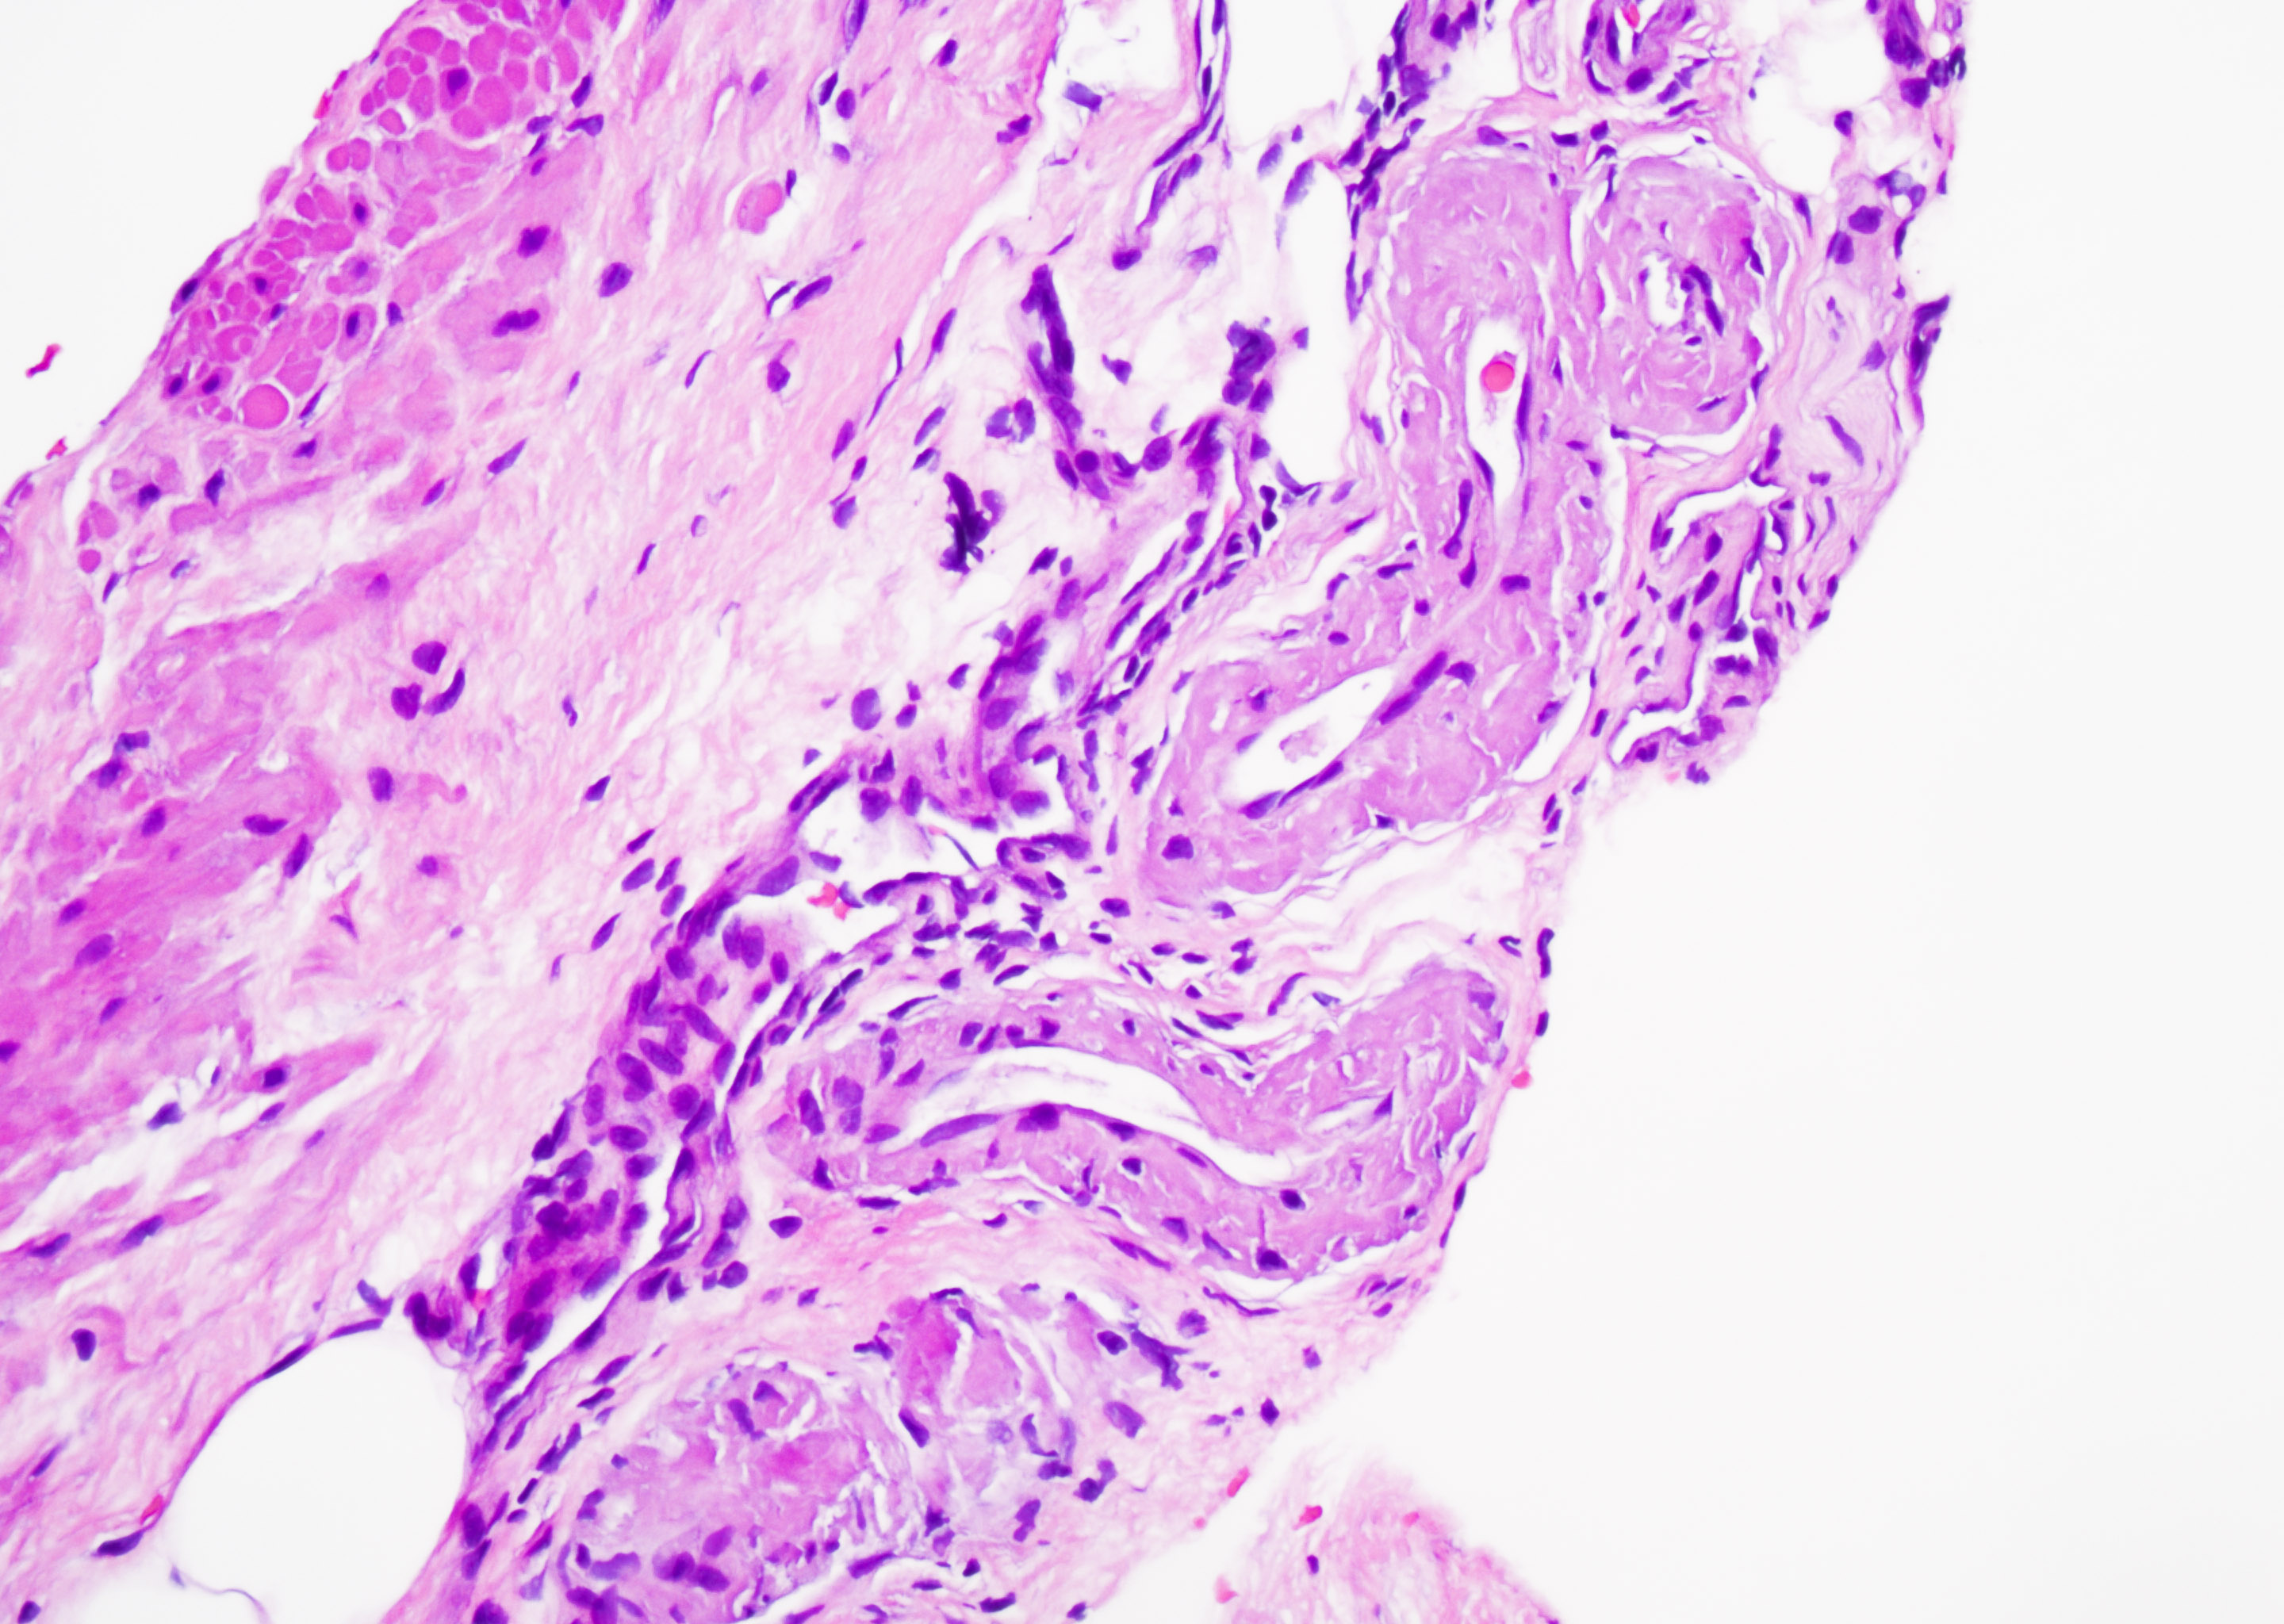

Vulvar skin biopsy. Erythematous pruritic eruption. Your diagnosis?

Only H&E stain needed for this one!